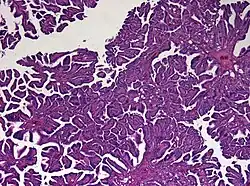

Histologie

Das feingewebliche Bild ähnelt mit Ausbildung papillärer Strukturen weitgehend dem des normalen Plexus choroideus. Tumoren, die atypische histologische Eigenschaften (insbesondere eine erhöhte mitotische Aktivität) aufweisen, werden als atypisches Plexuspapillom bezeichnet.[5]

Diagnostisch hilfreich ist der immunhistochemische Nachweis einer Expression des Zytokeratins CK7, Vimentin und S-100. Schwierigkeiten kann bei Erwachsenen die Abgrenzung gegenüber Hirnmetastasen bereiten. Der Nachweis einer Expression von plexustumor-spezifischen Markern kann dazu beitragen, die Verdachtsdiagnose eines Plexuspapilloms zu erhärten.[6][7]